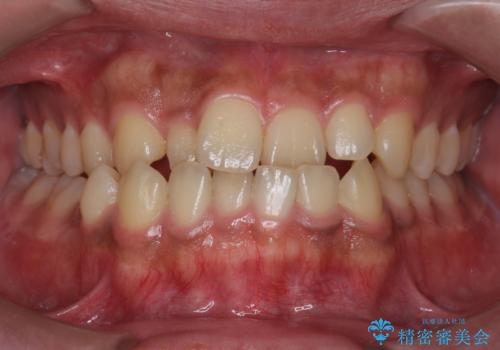

[ マウスピース矯正 ] がたがたした歯並びを治したい

担当医 大元洋佑

![[ マウスピース矯正 ] がたがたした歯並びを治したいの症例 治療前](https://seimitsushinbi.jp/wp/wp-content/uploads/2024/04/IMG_0106-500x350.jpg?v=1711951424)

![[ マウスピース矯正 ] がたがたした歯並びを治したいの症例 治療後](https://seimitsushinbi.jp/wp/wp-content/uploads/2024/04/46939b7482334672d3a091da1562afec-500x350.jpg?v=1711951403)